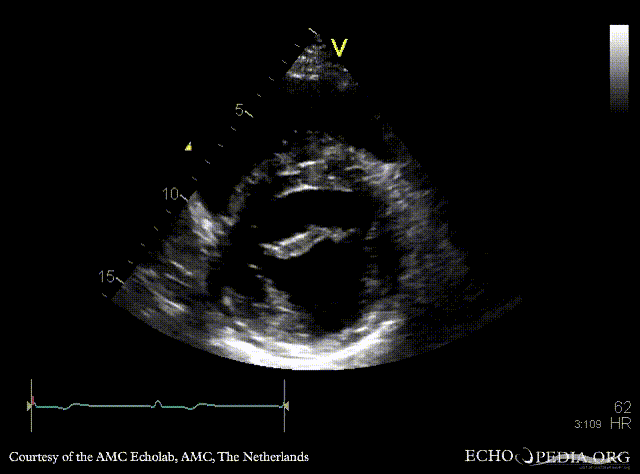

| Marfan Syndrome

| PLAX: dilated aortic root, redundant mitral valve leaflets

PLAX: dilated aortic root